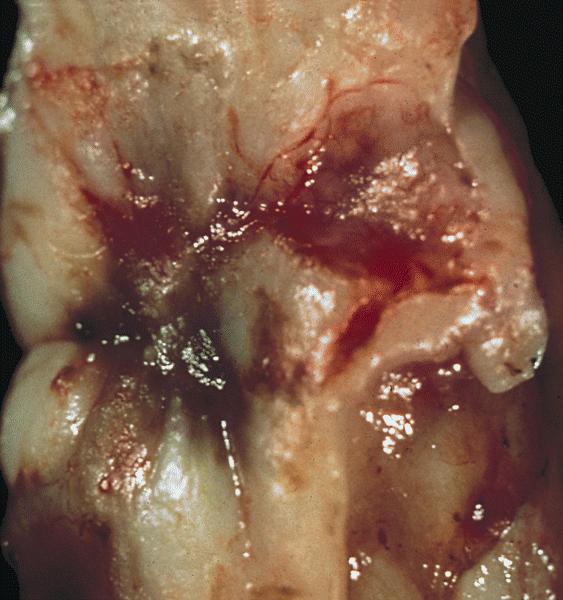

Gross description

- Ovarian endometriotic cysts (endometriomas) have fibrotic walls, a smooth lining and dark brown cyst contents (chocolate cyst), often adherent to adjacent organs

- Polypoid endometriosis has a polypoid configuration that raises the differential diagnosis of a neoplasm on gross and intraoperative examination (Am J Surg Pathol 2004;28:285)

- Red, brown, white plaques, sometimes with a gelatinous appearance (Arch Gynecol Obstet 2015;292:1295, Taiwan J Obstet Gynecol 2019;58:328)

Gross images